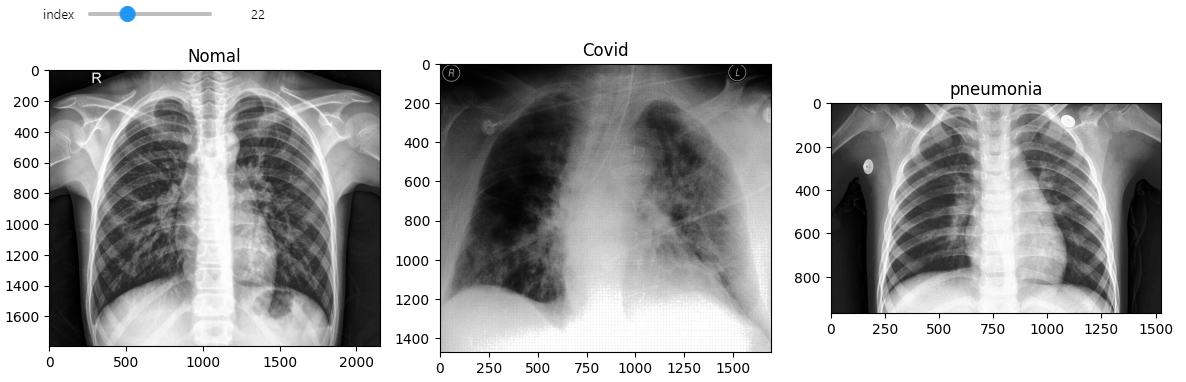

@interact(index=(0, min_num_files-1))

def show_samples(index=0):

normal_image = get_RGB_image(data_dir, test_normals_list[index])

covid_image = get_RGB_image(data_dir, test_covids_list[index])

pneumonia_image = get_RGB_image(data_dir, test_pneumonias_list[index])

prediction_1 = model_predict(normal_image, model)

prediction_2 = model_predict(covid_image, model)

prediction_3 = model_predict(pneumonia_image, model)

plt.figure(figsize=(12,8))

plt.subplot(131)

plt.title(f'Normal, Pred: {class_list[prediction_1]}')

plt.imshow(normal_image)

plt.subplot(132)

plt.title(f'Covid, Pred: {class_list[prediction_2]}')

plt.imshow(covid_image)

plt.subplot(133)

plt.title(f'Pneumonia, Pred: {class_list[prediction_3]}')

plt.imshow(pneumonia_image)

plt.tight_layout()